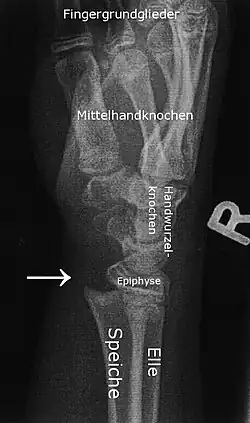

Epiphysiolyse der distalen (körperfernen) Radiusepiphyse (Speichenepiphyse). Weitere Erklärungen siehe Abschnitt Bilderklärung.

Auf dem linken Bild sieht man die frische Epiphysiolyse. Die distale (körperferne, also handgelenknahe) Epiphyse des Radius (Speiche) ist so verschoben, dass der Radius selbst nach palmar (handinnenflächenseitig) verschoben ist. Der Pfeil im Bild zeigt genau auf die Stufe, die dadurch entstanden ist.

Für den ungeübten Betrachter mag verwirrend sein, dass Speiche und Elle (Radius und Ulna) auf diesen Aufnahmen hintereinander liegen und wegen ihrer relativen Durchsichtigkeit im Röntgenbild beide sichtbar sind.